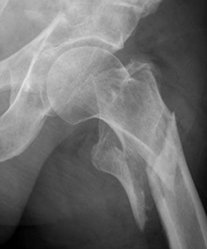

Fig 47. Fractura.

A: Rx AP. Línea radiolúcida en la cabeza femoral, sugestiva de fractura.

B: RM coronal en T1 y C: RM coronal en STIR. Edema óseo en la cabeza femoral, con imagen hipointensa y en sentido oblicuo, que corresponde a fractura.